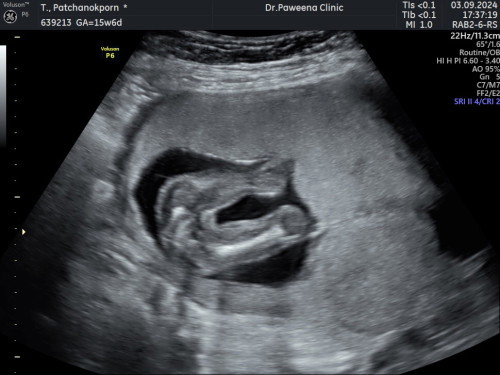

คิดว่าหญิงแน่นอนรึป่าว

ซาวด์ตอน 16W หมอบอกหญิงแน่นอน มีโอกาสจู๋โด่มั๊ยคะ

ชัดเจนค่ะ หญิง แน่นอนค่ะ ถ้าชายอ้าแบบอย่างงั้ยจู๋ก็เห็นค่ะ

ไปซาวคลินิคมา เรียบเหมือนกันเลยหมอฟันธง ญ

น่าจะแต่นอนนะค่ะไม่เห็นไข่

หญิง 100% ค่ะ